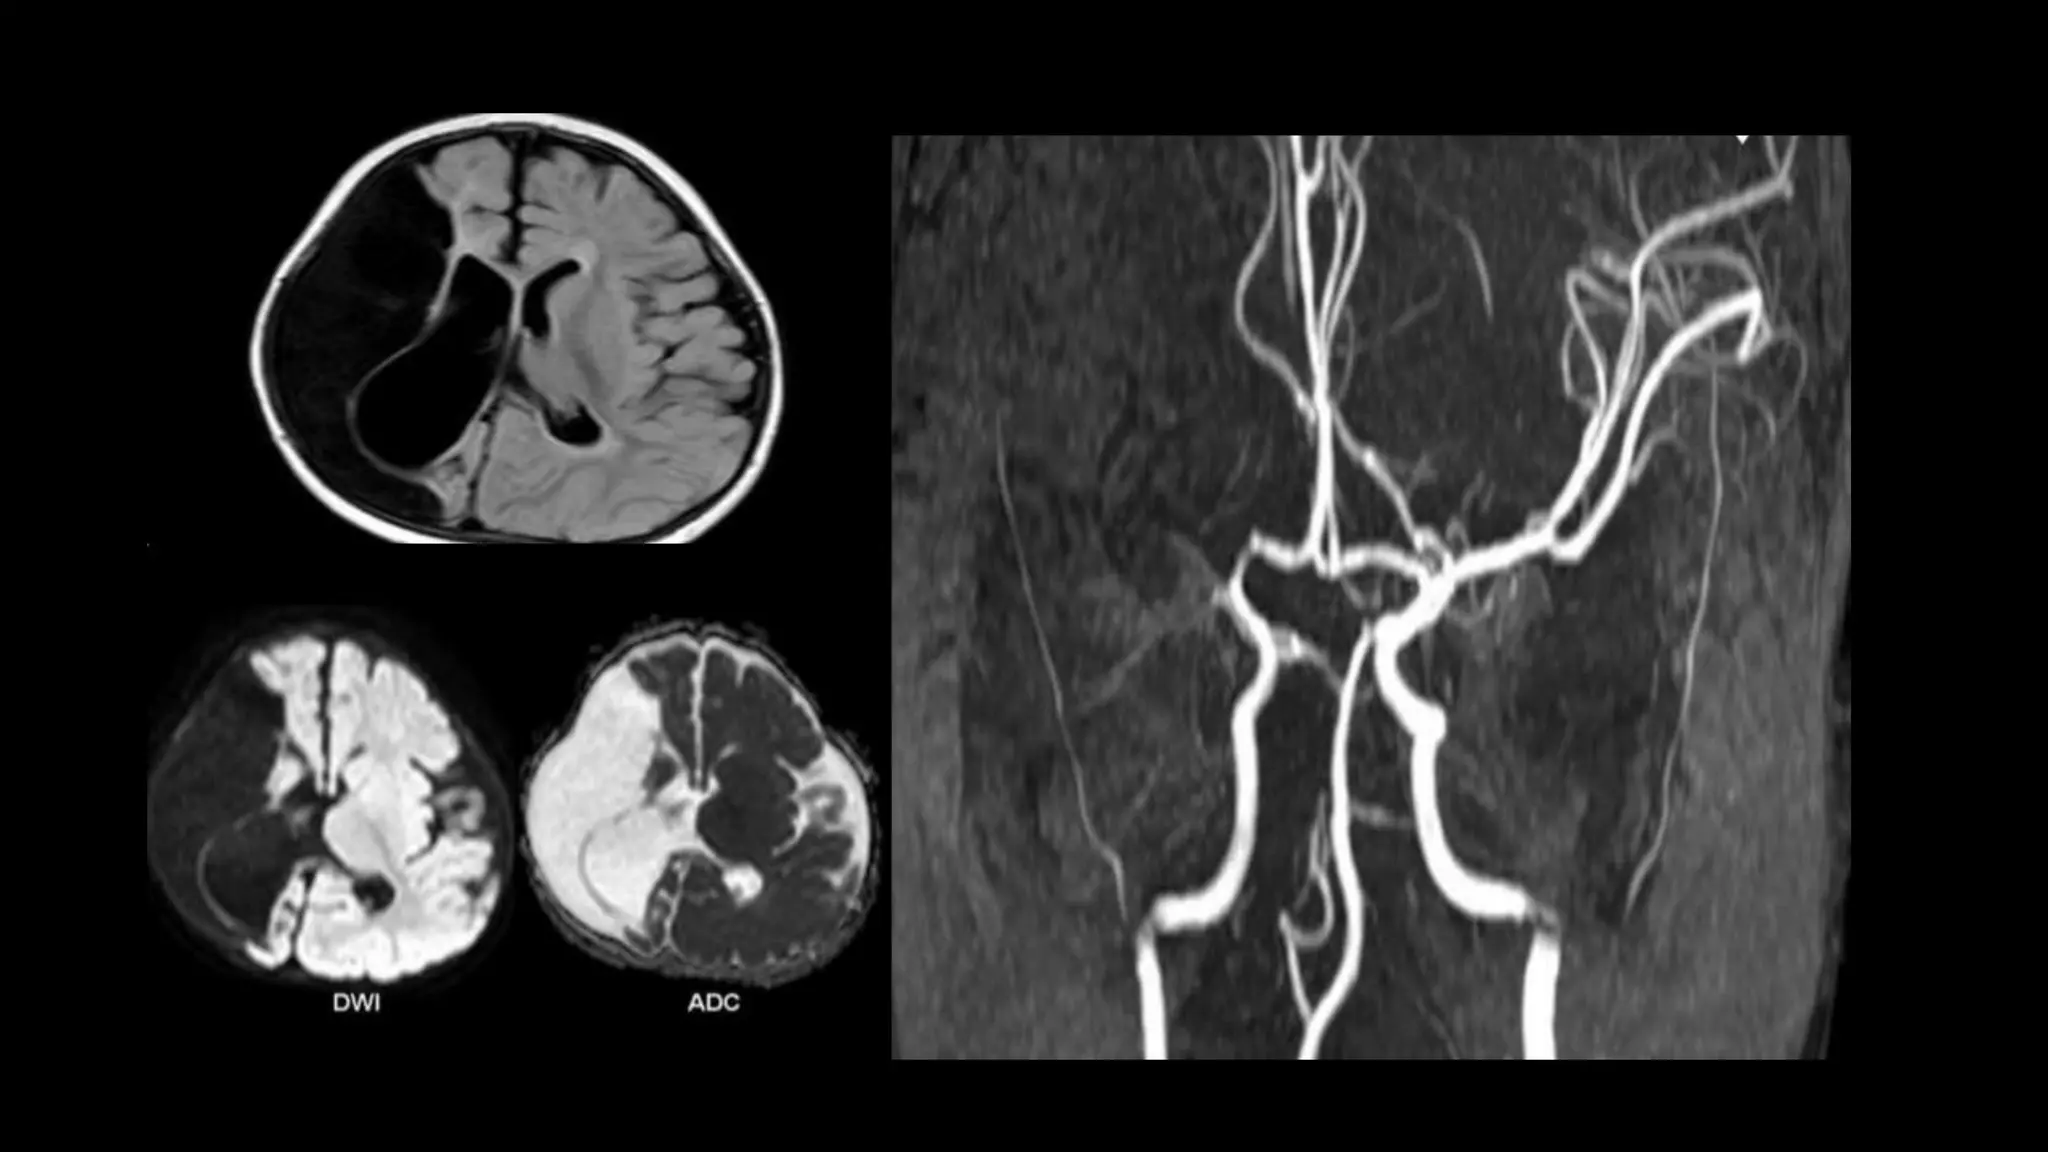

• #75 This is an example of 51y woman with sudden onset of speech difficulties and right side weakness, FAST FLAIR sequence shows left MCA cortical hyperintensity . DWI shows restricted diffusion in the corresponding areas

• #76 T2* GRE in the same case shows blooming thrombus in the left M1 segment till bifurcation. Perfusion MR shows markedly reduced cerebral blood flow in the densely ischemic core infarct which appears smaller than the corresponding DWI and FLAIR abnormality